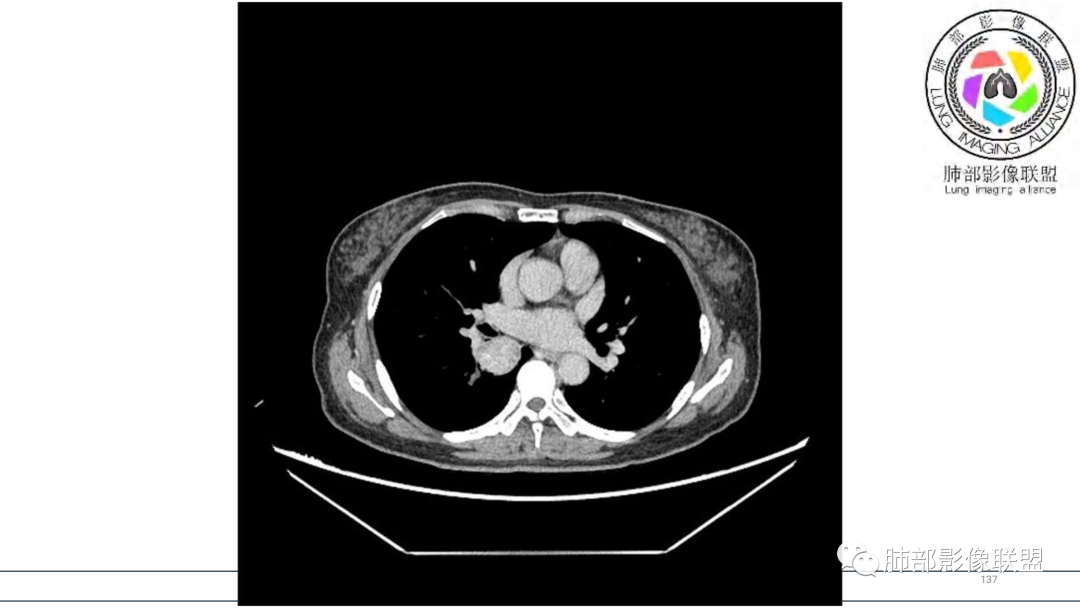

2.右肺下叶及中间段支气管后方类圆形块影,边界较清楚,未见分叶及毛刺,病灶部分突入支气管腔内(冰山一角),局部管腔狭窄,相应肺叶未见片影或体积变化。

3.块影密度均匀,未见液化坏死及钙化,渐进性强化,强化显著。

中青年女性,支气管管腔内外肿块(“冰山征”),边界较清楚,强化显著,未见阻塞性肺不张,尽管未出现“类癌综合征”临床表现,仍然符合典型类癌影像学表现。